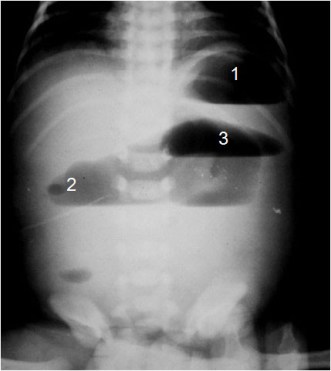

SIGNO DE LA TRIPLE BURBUJA

En la obstrucción yeyunal congénita (atresia), el gas y el líquido se acumulan en el estómago (1), el duodeno (2) y el yeyuno proximal (3), apareciendo una triple burbuja en la radiografía simple de abdomen. La imagen es patognomónica.